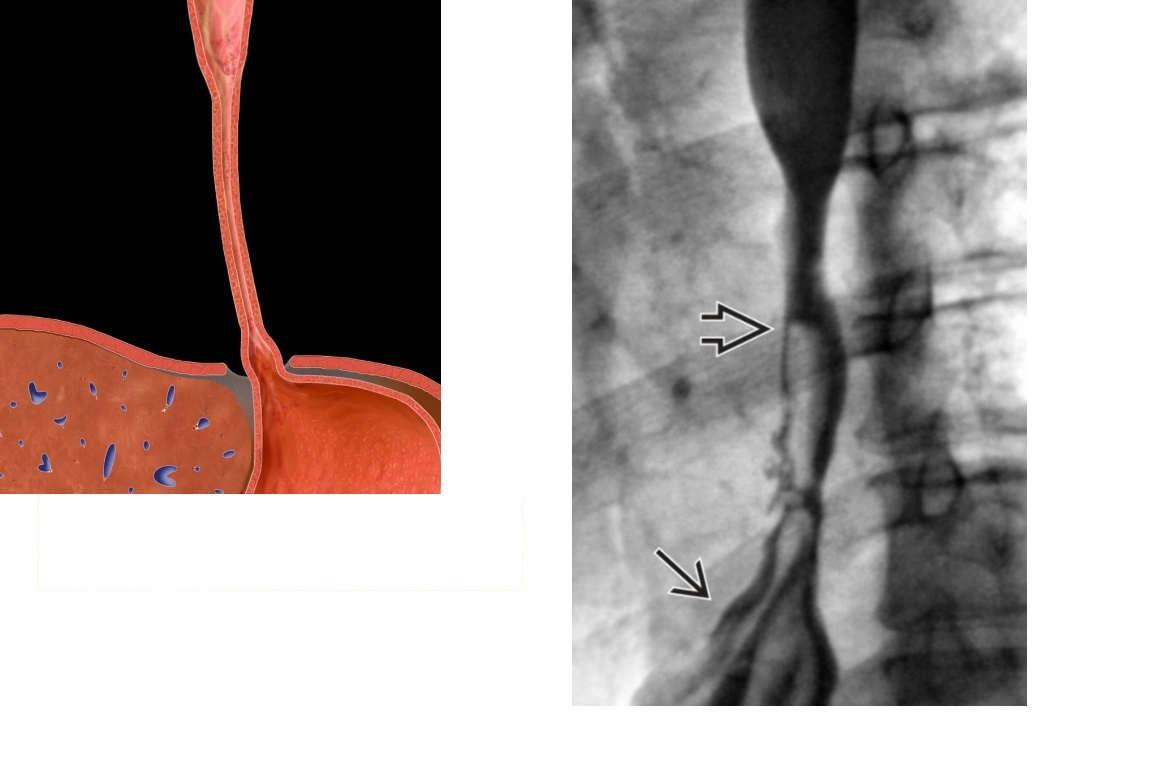

oesophageal scleroderma

-affects the Lower 2/3 (smooth muscle) with atony and peristalsis that begin caudally and moves cranially.

-Moderate dilatation of esophagus with fusiform stricture at lower end

Nb upper 1/3 to above aortic arch is normal (striated muscle)

Achalsia

- Grossly dilated whole oesophagus with smooth, beak-like tapering at lower end

Reflux Esophagitis (With Stricture)

-Longer tapered distal stricture

-Less luminal dilation

-Distinguished from scleroderma by normal peristalsis

Esophageal Carcinoma

-Abrupt proximal borders of strictured segment (rat tail appearance)

-Mucosal irregularity, shouldering, mass effect